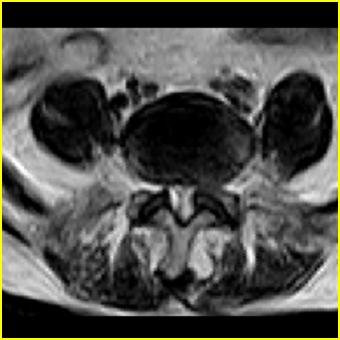

男,78岁,右下肢跛行两月.

右侧黄韧带肥厚或钙化,压迫马尾神经所致。必要时行ct扫描。

腰间盘膨出、黄韧带肥厚、可疑先天性腰椎管狭窄。